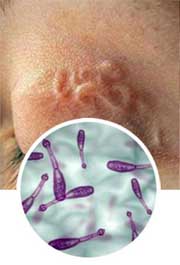

Parasites are multicellular protozoan organism, living at the expense of their host and make harm. Parasites first appear in intestines, then spread around the organism damaging all vital organs of a person:

Eye pathology, causing the eyesight deterioration.